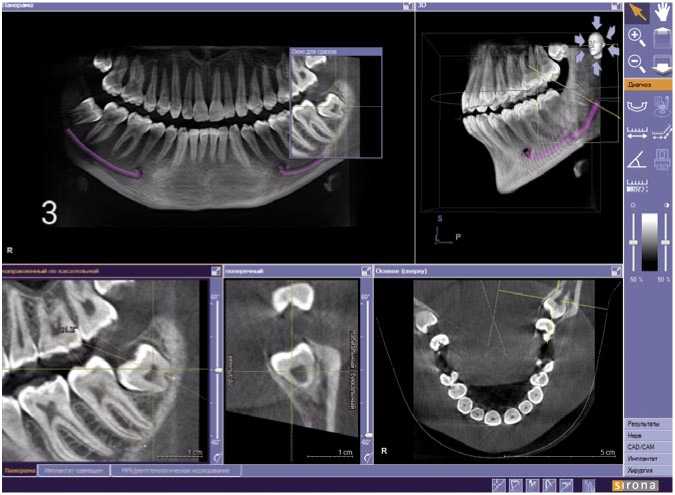

Далее КЛКТ-исследования зубочелюстной системы пациента К. проводили в динамике: КТ-1 в возрасте 16 лет (Рис. 1), КТ-2 – в 18 лет (Рис. 2) и КТ-3 в возрасте 19 лет (Рис. 3) с интервалами 28 и 6 месяцев, соответственно. При сравнении значений КТ-1 и КТ-2 выявлена положительная динамика изменения положения зуба 3.8 (уменьшение угла между зубами 3.7 и 3.8), рост корней в длину. Динамика на КТ-2 и КТ-3 была незначительна, что дает основание считать интервал между КТ-исследованиями менее 6 месяцев малоинформативным. В итоге, по истечению 3 лет наблюдений имеем изменение положения зачатка зуба 3.8 и тенденцию к самостоятельному прорезыванию.

Рис. 2. Пациент К., 18 лет. Срез компьютерной томограммы. Изменение положения зачатка зуба 3.8.

Рис. 3. Пациент К., 19 лет. Срез компьютерной томограммы. Зуб 3.8 на этапе прорезывания.

ми третьими молярами, в отличие от пациентов с ретенированными зубами, что может быть возможной причиной ретенции [2; 8].